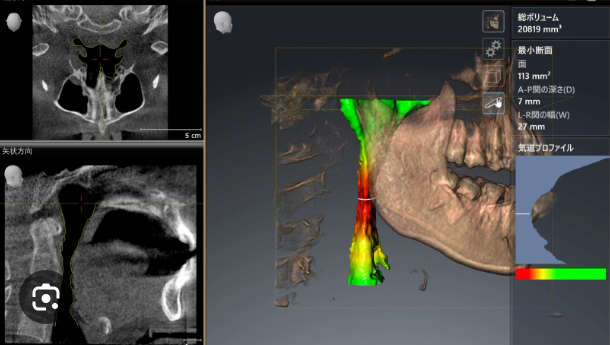

このCTは、今までCTが診断できた骨の状態、欠損の状態、顎関節、歯根の膿、親知らず、上あごの炎症、神経の走行を高密度な画像構築することでより高度な診断も可能にしています。

加えて業界初の気道の広さも3Dで診断することにより今まで不可能であった睡眠時無呼吸症候群のリスクも計測し診断することが可能になりました。

高精細な3D画像を取り入れることで、口腔内を立体的に観察し、骨の位置や量、病巣の大きさなど診断に重要な要素を把握することができます。

気道の状態を

3D画像で診断

今まで歯科のCTでは診断できなかった気道の状態を3D画像で診断することが可能になりました。 睡眠時無呼吸症候群の患者さんに対して、正確な診断・治療計画がおこなえます。